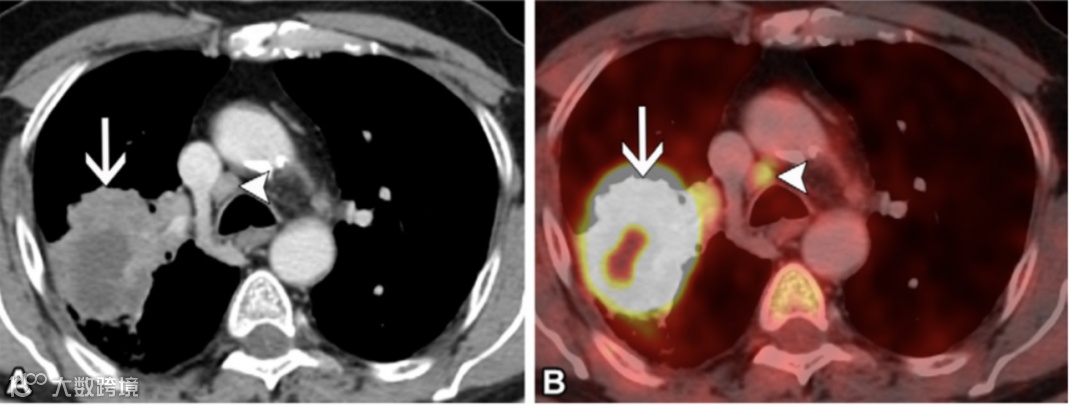

图8. 54岁男性非小细胞肺癌(NSCLC)患者的N1期病变。

(A)轴位增强胸部CT图像(软组织窗)显示右上叶原发肿瘤(箭头)以及右肺门10R站点的单个转移性N1淋巴结(短箭头)。

(B)与A图像相同水平的轴位融合氟代脱氧葡萄糖(FDG)PET/CT图像显示该淋巴结(短箭头)呈FDG高摄取,代谢程度与原发肿瘤(箭头)相似。

图9. 65岁男性非小细胞肺癌(NSCLC)患者的N2a期病变。

(A)轴位增强胸部CT图像(软组织窗)显示右上叶原发肿瘤(箭头),并且在同侧气管旁4R站点发现单一站点的转移性N2淋巴结(短箭头)。

与A图像相同水平的轴位融合氟代脱氧葡萄糖(FDG)PET/CT图像(B)显示该淋巴结(短箭头)呈FDG高摄取,类似于原发肿瘤(箭头)。